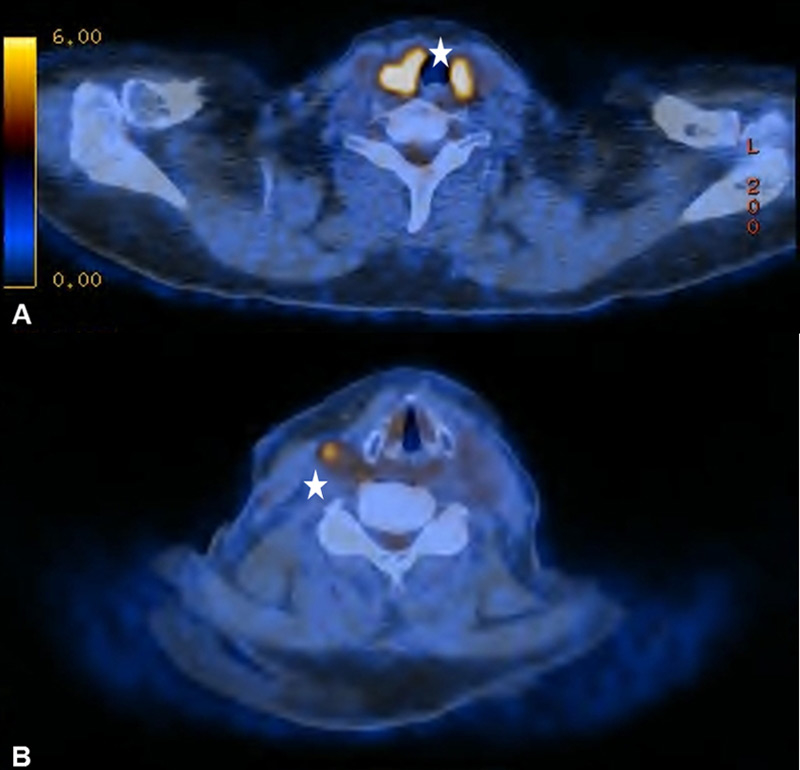

Figure 1

(A) Bilateral physiological uptake in the palatine tonsils in a 83-year old patient with a past medical history of a floor of nose melanoma. (B) Symmetric increased uptake in the muscles of mastication in 71-year old patient treated for tonsillar carcinoma.

It is known that PET-CT is more accurate in detecting HNC recurrence than conventional physical examinations alone and that therefore negative periodic clinical examinations may be complemented by FDG PET-CT [8, 15]. As expected, we observed PET-CT to be a well-established ruling-out test at the expense of a decreased positive predictive value and specificity [7–9]. However, interpretation of indistinct FDG-positive findings remains challenging because of a high number of false-positive lesions and the necessity for potentially unnecessary and invasive diagnostic investigations. As in previous studies, we found typical foci of increased FDG uptake [16, 17]. The pharyngeal mucosa frequently causes physiological FDG uptake, hence the interpretation is usually unproblematic as long as the uptake is located superficially along the mucosal plane in linear configuration [18]. The palatine tonsils and other lymphatic structures of the Waldeyer’s ring typically exhibit FDG uptake, which most likely reflects a so-called “physiological inflammation” of the lymphatic tissue due to confrontation with antigens [18, 19] (fig. 1A). Furthermore, muscles of mastication and intrinsic tongue muscles were shown to be highly sensitive to exogenous confounders such as chewing gum during examination and therefore a good quality of PET-CT/MRI clearly depends on the compliance of the patient [20, 21] (fig. 1B). With regard to the floor of mouth (FOM) muscles, a recent study investigating the effect of a supine versus a sitting position on physiological FDG accumulation, did not find any alterations and concluded that there is no trick to avoid or reduce this kind of disturbing FDG uptake [22]. The correlation between muscular activity and increased FDG uptake was also shown for the larynx, since talking can cause FDG uptake in the muscles of phonation as well as in the vocal cords [18, 23]. In terms of FDG uptake in the salivary glands, the parotid, submandibular and sublingual glands may all reveal mild to moderate symmetric or asymmetric uptake, although these findings underlie a marked inter-individual variability [16, 17]. As there is a close relationship between reduction in FDG uptake into the salivary glands and increasing doses of RT, we found five patients with asymmetric salivary gland FDG uptake due to surgical treatment and RT to the contralateral side [24] (fig. 2A). Similarly, we observed four patients with asymmetric FDG uptake in the tongue and FOM as a consequence of muscular imbalance due to contralateral surgical treatment (fig. 2B). Another well-known phenomenon is the increased FDG uptake in the contralateral vocal cord if a recurrent laryngeal nerve palsy is present (fig. 3AB).